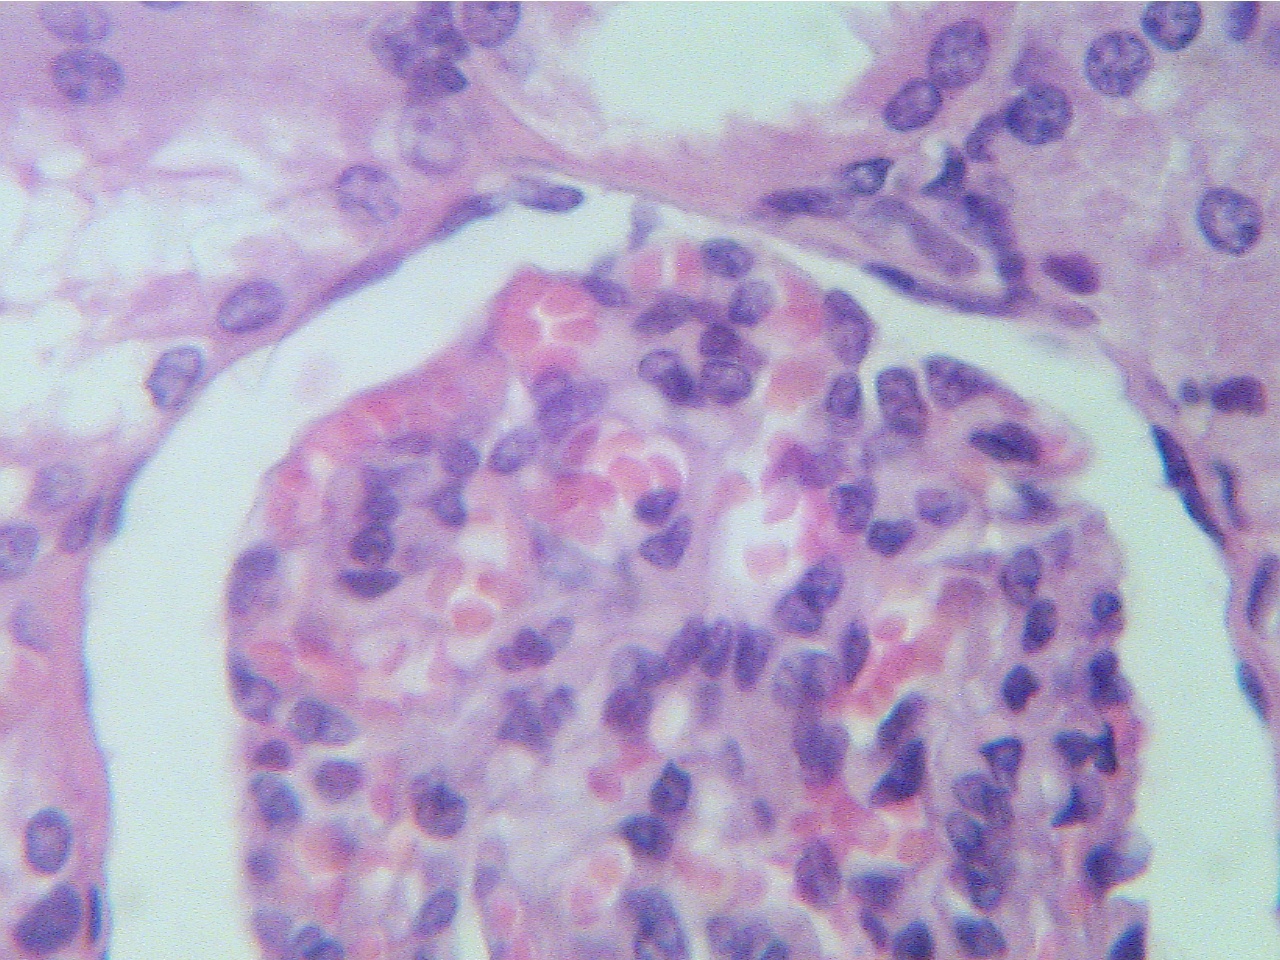

Glomerulus (400X2.8)

Note the numerous dark blue nuclei of the

cells

making up this glomerulus. The opening from

the

glomerular cells. Observe the capillaries containing

Bowman's capsule of this glomerulus to

red RBCs, which have no nuclei.

proximal convoluted tubule can be seen at the top

of the capsule.